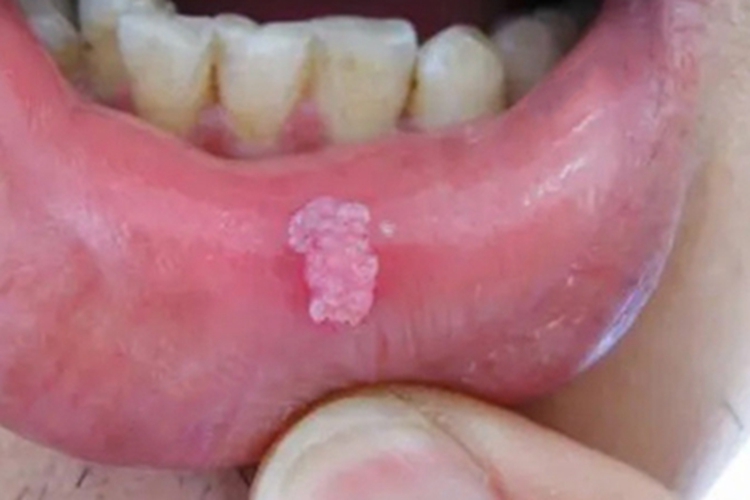

少数尖锐湿疣患者的唇内侧可受累,出现肉赘样损害,表面呈颗粒状,质地柔软,由HPV感染导致,需遵医嘱治疗。

少数尖锐湿疣患者的唇内侧可长肉赘样损害,无蒂,表面呈颗粒状,颜色为淡粉色,摩擦后会出血,后渐增多增大,质地柔软,多数患者无明显自觉症状,少数可有异物感、灼痛等不适。